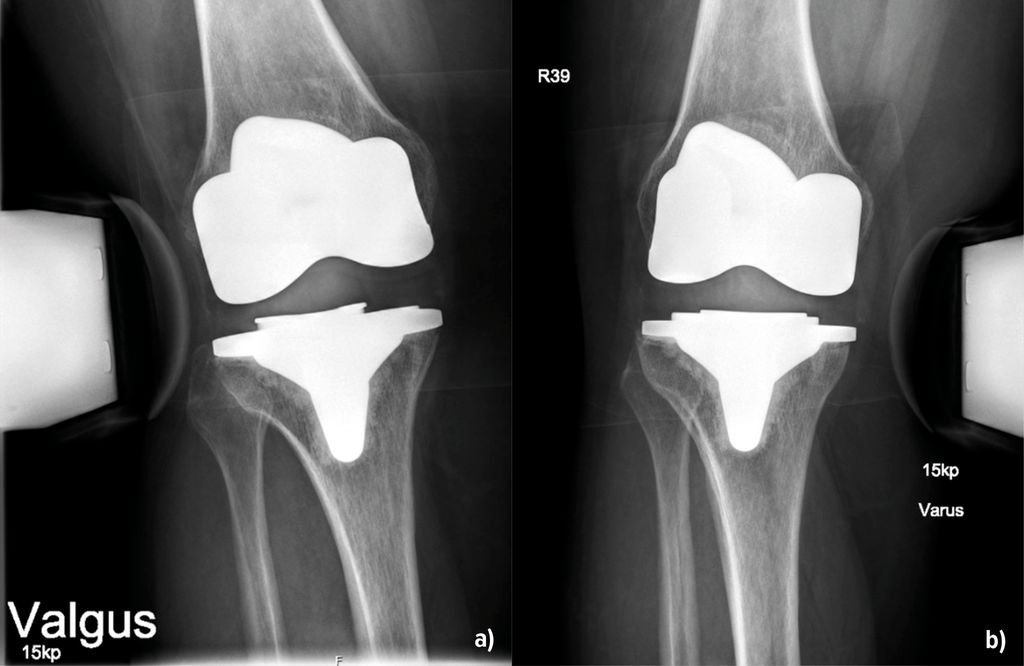

Abb. 2: 53-jährige Patientin 14 Monate nach KTEP-Implantation mit klinisch und radiologisch (a und b) nachweisbarer Instabilität – medial stärker als lateral

Die Instabilität von Knietotalendoprothesen beeinflusst die Zufriedenheit der Patient:innen und führt häufig zu Revisionseingriffen. In einer grossen retrospektiven Studie mit Erfassung von fast 40000 Patient:innen aus den Jahren 1996–2021 konnten Ergin et al. (2025) Risikofaktoren, welche mit einer Instabilität nach Endoprothetik einhergehen, darstellen. Dazu gehörten ein jüngeres Alter, das weibliche Geschlecht, ein Schlaganfall, tiefe Beinvenenthrombosen, Nickelallergie, Osteoporose und – überraschend – die Sklerodermie. Die Adipositas stellt demnach kein erhöhtes Risiko dar. Über die Details der Ursachen berichtet die Arbeit allerdings nicht, sondern beschreibt diese als multifaktoriell. Jedoch können die Autoren aus der eigenen klinischen Praxis berichten, dass durchaus Unterschiede in Bezug auf das Inlay bestehen. Entweder war dieses primär zu flach oder es ist zu einer Lockerung der Bänder im Verlauf gekommen. Auch der Verschleiss des Inlays über die Zeit spielt erfahrungsgemäss eine Rolle (Abb. 1). Bei der Differenzierung, welches Ausmass einer Varus- oder Valguslaxizität zu einem annehmbaren oder schlechten klinischen Ergebnis führt, fanden Mitsu-Uchi et al. (2025), dass eine mittlere Instabilität von 3–6mm im medialen Kompartiment für ein besseres postoperatives Ergebnis von Bedeutung sei. Eine straffe Implantation mit einer Instabilität von <3mm sowie Instabilitäten von >6mm führten demnach zu niedrigeren Zufriedenheitswerten bzw. Knee-Scores. Somit soll eine mittlere mediale Laxizität für ein besseres postoperatives Ergebnis sorgen, was bereits bei der Implantation Beachtung finden kann. Neben dem klinischen Nachweis ist die gehaltene Röntgenaufnahme geeignet, um den Befund zu verifizieren und zu dokumentieren (Abb.2). Bezüglich der Ursachen für Fehlschläge primärer Knietotalendoprothesen finden sich die Instabilitäten mit einer Häufigkeit von 7% bzw. 4,55% an 3. bzw. 4. Stelle. Vorwiegende Gründe für Revisionen sind hingegen periprothetische Infektionen (22,3% bzw. 47,73%), die aseptische Lockerung (20,5% bzw. 35,23%) und Bewegungseinschränkungen (5,68%) (Datta et al. 2025, Mozella et al. 2024). In einer Arbeit von Poilvache et al. (2025) wurde das Übergewicht als Risikofaktor für Komplikationen nach K-TEP untersucht. Die Hauptursachen für die initiale Revision waren die aseptische Lockerung mit 37%, die Instabilität (29%) und der Abrieb oder Osteolysen (13%). Die Arbeit erbrachte ganz klar, dass ein BMI >40kg/m2 tendenziell mit einer Reoperation korrelierte. Allerdings nicht wegen Instabilität, sondern wegen periprothetischer Infektionen, und das auch nicht signifikant. Der BMI als Ursache einer Instabilität nach Revision wurde hier ausgeschlossen. Brown et al. (2025) beschrieben ein erhöhtes Risiko mit Hinblick auf eine Revision als Folge einer Instabilität oder einer Lockerung bei Fällen, in denen die Femurkomponente grösser als die Tibiakomponente war. Die Autoren empfahlen, primär die Wahl der Prothesengrössen zu beachten, um Instabilitäten vorzubeugen. Auf die Infektionsraten und den anterioren Knieschmerz fand sich in dieser Kohorte kein Einfluss.